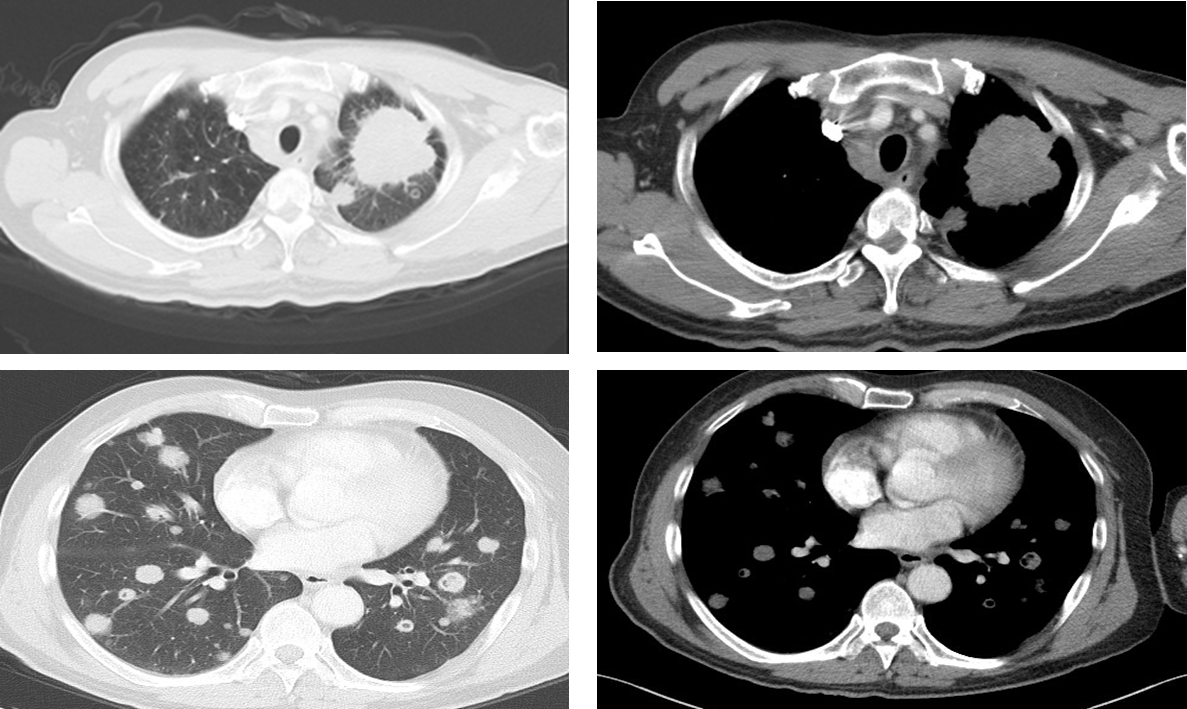

2019-1-8当地医院开始接受一线化疗2周期,方案为TP (多西他赛 120mg d1+洛铂 50mg d2)。化疗2个周期后于2019-02-18复查胸部增强CT示:左肺癌,双肺转移,左侧叶间胸膜增厚,考虑转移;双肺门、纵隔淋巴结转移。疗效评价结果:PD;PFS为1个月。

image003.png

图2. 一线化疗2个周期后复查